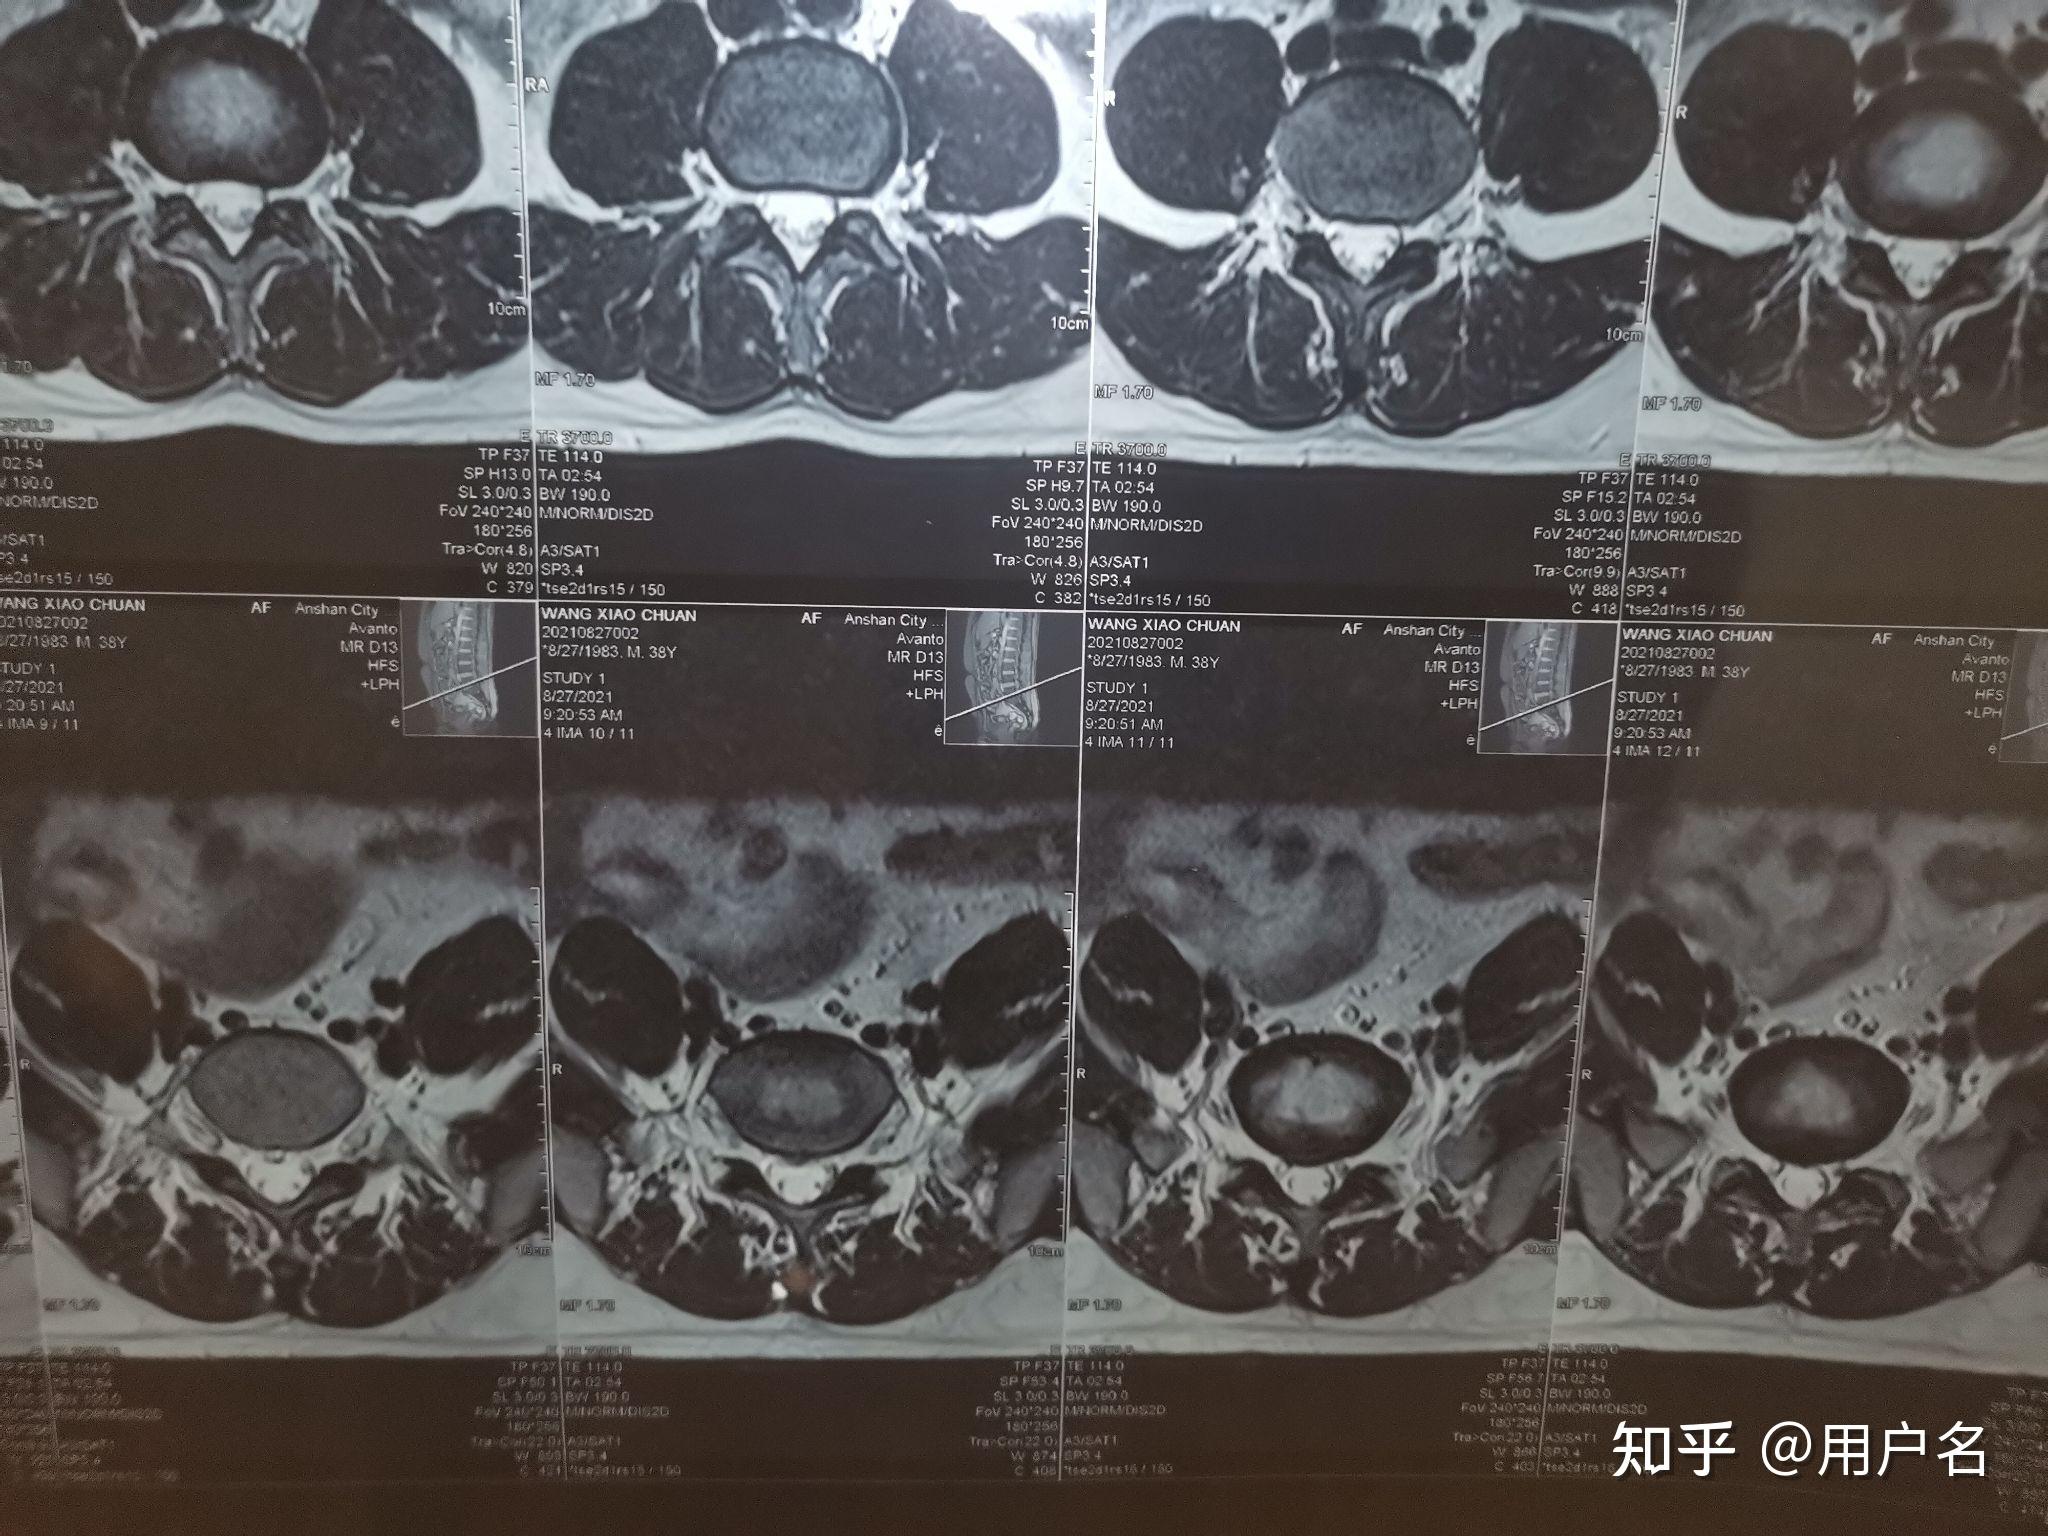

l5s1腰椎间盘突出哪位大神帮我看下严重么有没有压迫到神经之类的跪谢

腰椎间盘突出l5s1中央型求帮助